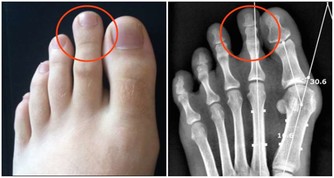

我們能不­能從外表找到發病的前兆呢?

答案當然是肯定的,但是要怎麼看呢?